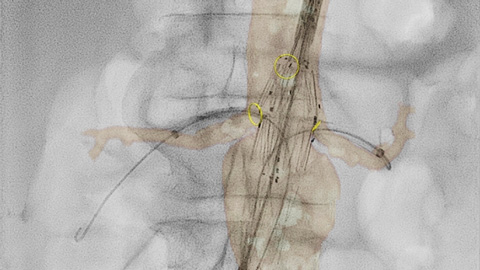

En el laboratorio integrado de Azurion, los equipos de radiología intervencionista pueden acceder fácilmente a la medición y visualización 3D avanzadas de SmartCT, y a la imagenología intravascular (IVUS) de IntraSight en una pantalla táctil en la mesa para ahorrar tiempo y mejorar la confianza clínica.

El módulo de pantalla táctil (TSM) mejorado le permite controlar, de manera fluida, una amplia gama de herramientas de intervención multimodal, incluida la visualización y medición 3D avanzadas de SmartCT, el ultrasonido intravascular (IVUS) digital de instalación automática de IntraSight y otras herramientas compatibles de procedimientos específicos dentro del campo estéril. Esto reduce las interacciones y la necesidad de caminar de un lado a otro entre las diferentes consolas y la sala de control, para iniciar una aplicación o realizar una medición durante los procedimientos de radiología intervencionista.

A través de la herramienta del marcador en la pantalla táctil, puede señalar un área de interés en las imágenes 2D. Las marcas se muestran con claridad en la fluoroscopia y las imágenes de referencia, y se escalan y desplazan con la imagen. Esto puede ser útil para marcar una bifurcación, ramas laterales y otros detalles relevantes. Con la herramienta del marcador, no hay necesidad de una aplicación de marcador independiente en el laboratorio.